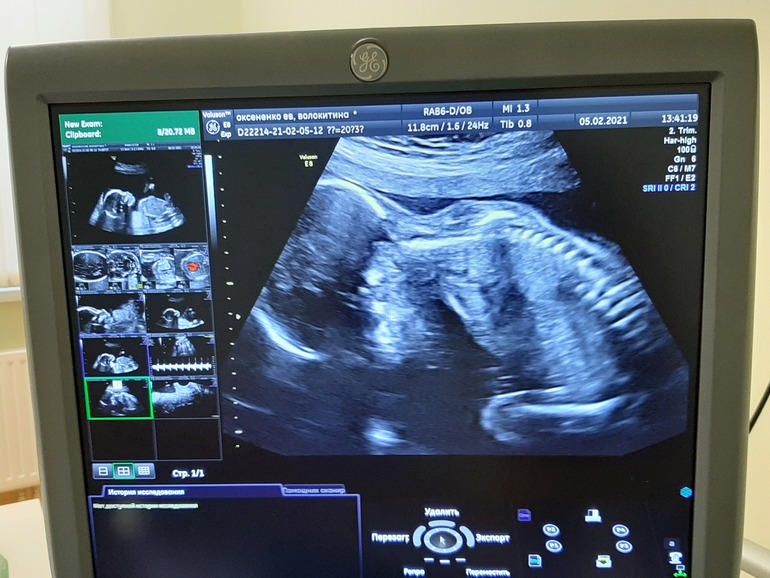

Ах ну и фото, с монитора правда, нашей Евишны-королевишны, оооох так и приалепится имя 🤷♀️....

Говорю, на меня похожа, врач посмотрела говорит, нет нос не ваш 🤣🤣🤣. Чтобы она понимала 🙈🤣

Ну да ладно. Пришла на УЗИ, врач смотрела в основном молча, напряглась не много, но не много терпения, как все замеры сделала, только потом задала ей несколько вопросов, по УЗИ все хорошо сердечко 151 чсс, спросила кто там)), она сказала мне кажется девочка, таааак как это кажется 🤣, переспрашиваю: "Точно?" Она улыбается и между делом: "Точно!". А мне снова не верится)))) Но других вариантов нет, я с первого дня чувствую дочку, боюсь поверить, но там точно не парень😂.

336 гр, нашего счастья😍😍😍!!